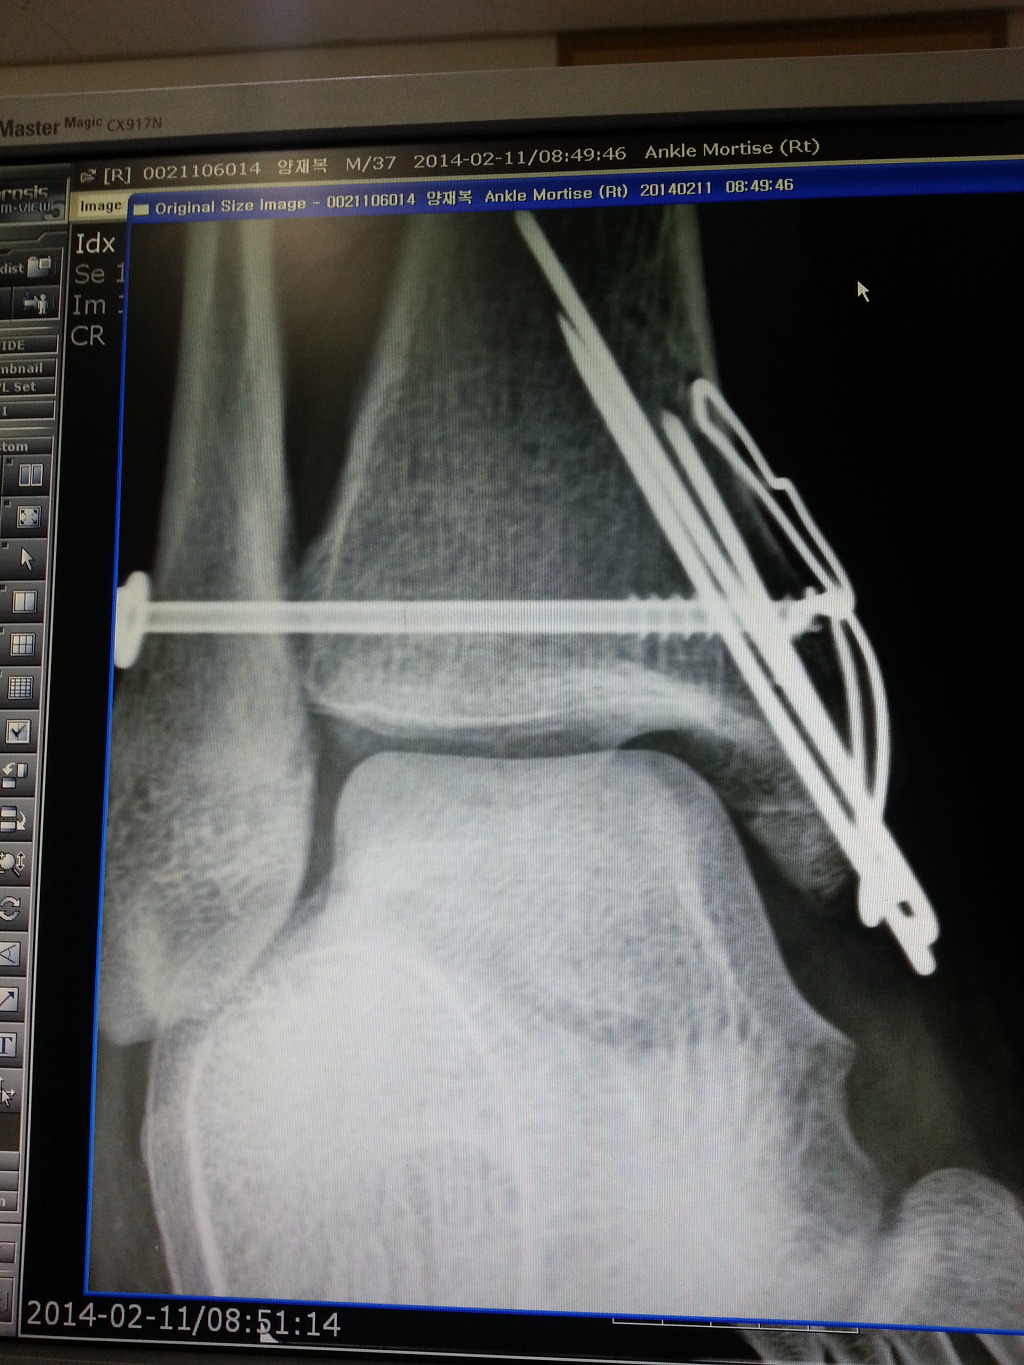

빙판에서 넘어져 양과골절로 2013.12.31.사진과같이 수술하였구요

8주후 발목에 있는 피스를 제거하였습니다.

그런데 이번에는 2014.6.4.일 5개월 넘어서면서 오른발안쪽복숭아뼈의 핀 3개 제거수술을 하시자고하네요